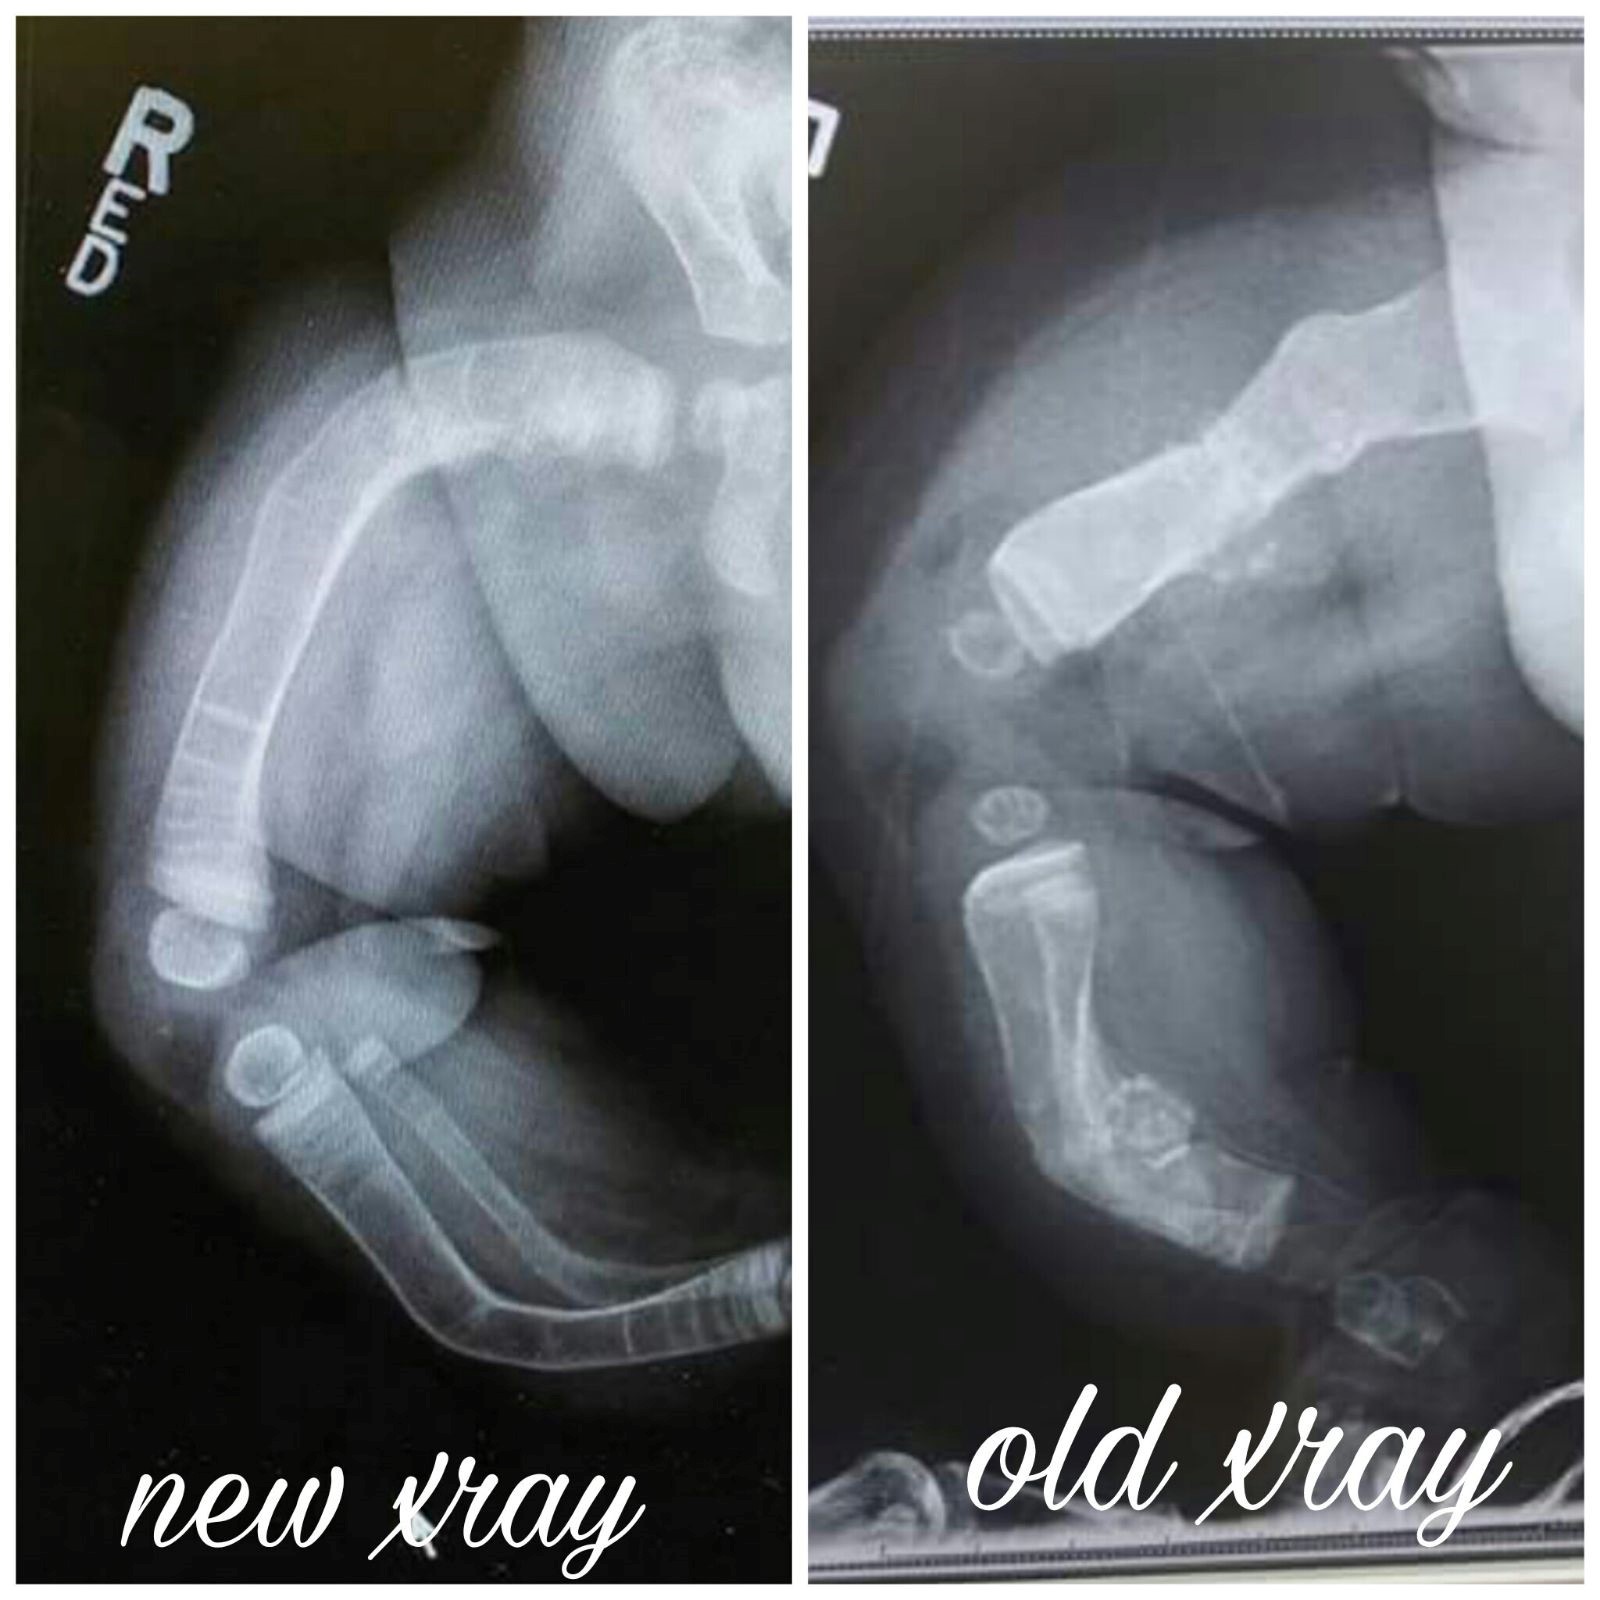

It is with great pleasure, we introduce Oliver Cope as the Celebrity Child for The 62nd Annual Variety Kids Telethon! Oliver was born on March 25th, 2016 and is seven years old.  He lives in Blasdell, N.Y. with his mother (Amanda), father (Eric) and ten year old sister, Frankie!  By just age 2, when many children are littered with bumps and bruises from exploring the world, Oliver had already experienced 31 broken bones. Born with osteogenesis imperfecta (OI), Oliver’s bones are extremely brittle, which causes them to break and fracture easily. Read more below on his resilient spirit and inspiring journey at Oishei Children’s Hospital (OCH) and The Variety Tent #7 Robert Warner, MD Center for Developmental Pediatrics and Rehabilitation.  At Amanda’s 20-week ultrasound, results came back that her baby, Oliver, had a femur that was broken. From there, Amanda had specialist appointments every month until he was born to keep an eye on his development. Doctors were initially confused as to why just his femurs appeared bent and broken. And then they realized his tibias were too short. And then they found that his arms were also underdeveloped. Specialists said it could be either osteogenesis imperfecta (OI), a rare genetic disorder that prevents the body from building strong bones, or dwarfism. Once Oliver was born, it was obvious he had OI. With 8 broken bones, he was in The Children’s Guild Foundation Neonatal Intensive Care Unit at Oishei Children’s Hospital (OCH) for 6 weeks and had 6 more breaks in that time. With Oliver’s condition, he can break a bone by just moving around or being held. Amanda recalls a time when he was just sitting on the couch and moved the wrong way, resulting in a sudden break. Another time, Amanda sat him up and accidentally broke a bone. And yet another time, she was putting him down for bed, scooping underneath him and accidentally broke his collarbone and shoulder blade – it just happens no matter how careful they try to be. Amanda estimates that Oliver has had 11 surgeries so far. His first was at a month old for a feeding tube and then a port for his infusions he was getting every two months, which since then has had to be replaced as it stopped working properly. He has had rods placed in both left and right femurs, tibias and humeri, which were three separate surgeries. The rods in his legs have already been replaced as he grew out of them. In the foreseeable future, Oliver’s arm rods will need to be replaced, but that surgery is down the road for him and his family. Oliver’s condition also causes brittle teeth. He has had caps placed to help protect some of his teeth and 6 other teeth removed as they were worn down. His last set of surgeries were for a new feeding tube along with a colostomy bag. Because his hips tip into the point where they almost touch, Oliver suffers from chronic constipation and a slower digestive system. He is always bloated and backed up, which is somewhat alleviated by his colostomy bag. However, his stoma for the same issue has caused him problems recently. It has prolapsed and herniated, calling for another surgery only a week after being inserted. Once that settled down, it was causing him irritation as it was too close to his skin, resulting in a third surgery. Currently, Oliver participates in physical therapy through The Variety Tent #7 Robert Warner, MD Center for Developmental Pediatrics and Rehabilitation at OCH. Initially fearful of coming and participating in hands-on therapy in fear of breaking a bone, he has grown to trust his physicians and is starting to enjoy his time there. He loves the big walker, working with his therapist and seeing friends that he has made. He is extremely excited to get started with water therapy! Some fun facts about Oliver whose family affectionately calls “Ollie”, include his excitement for building Legos!  He is the #1 fan of Kraft Mac & Cheese and loves the color Red. Sonic, the Hedgehog and Teenage Mutant Ninja Turtles are a few of his favorite things. He is truly a ray of sunshine with a smile that will light up any room.   Variety is thrilled to have Oliver Cope and his loving family a part of The 62nd Annual Variety Kids Telethon taking place Saturday, March 9th from 6pm-11pm on WGRZ, Channel 2 AND on Sunday, March 10th from 10am-8pm on WBBZ, Channel 5 and streaming online.   We hope you will tune in and learn more about Oliver Cope! Please kindly consider making a donation to the Variety Kids Telethon, today!